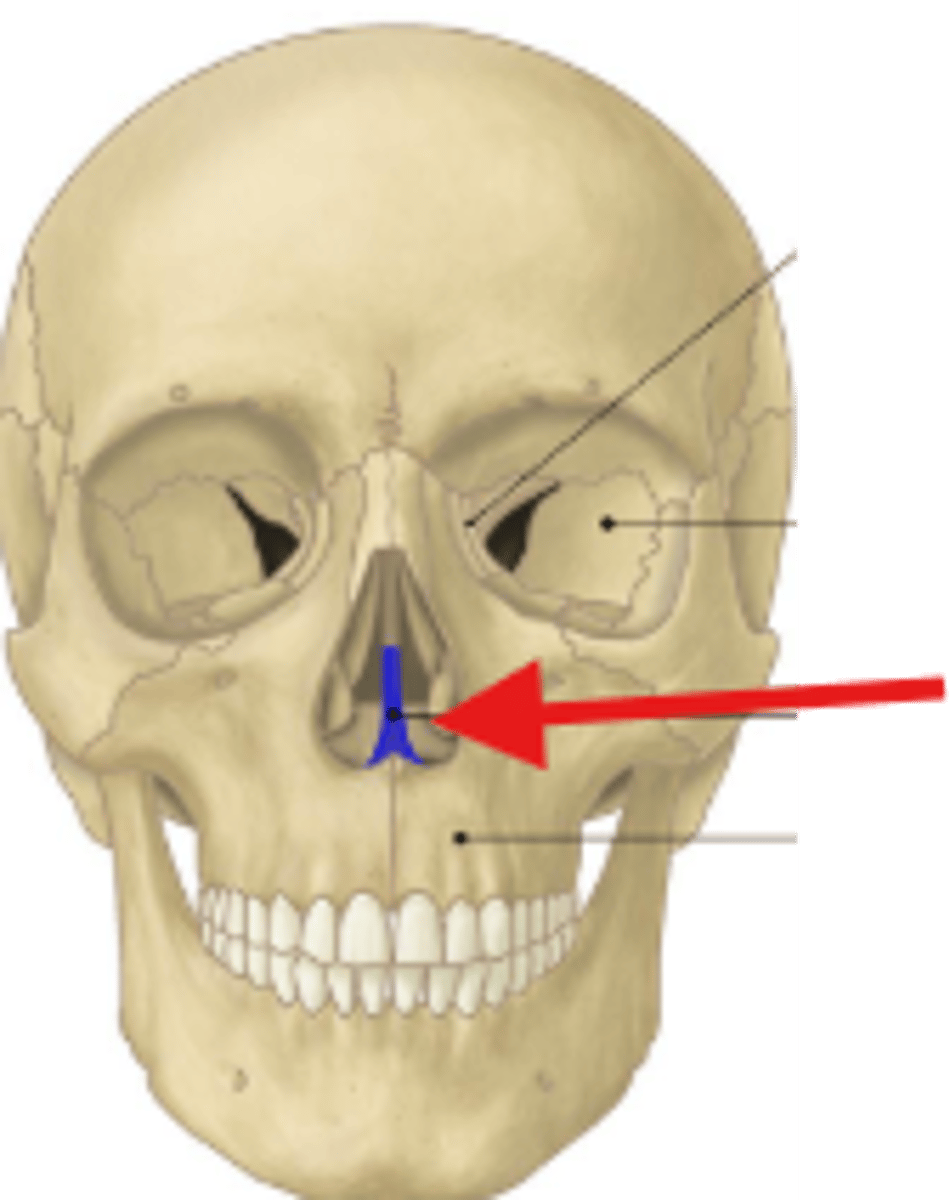

Name this bone (in blue)

What is the main name of the pink area?

Name one structure that comes from it?